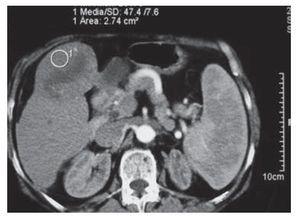

La evaluación de la respuesta al tratamiento se realizó por medio de tomografía computadorizada y marcadores tumorales. Se observó una respuesta total en 33.3% de los casos con evidencia de necrosis tumoral en más del 70% de la lesión mediante el uso de tomografía dinámica (Figura 2 y 3). En 66% de los pacientes hubo disminución significativa de los niveles séricos del marcador tumoral (alfa-fetoproteína o antígeno carcinoembrionario). Los niveles iniciales promedio de alfa-fetoproteina fueron de 169,122 ng/mL (rango 2 a 1 349 200 ng/mL) que contrastaron con los niveles promedio postratamiento de 35,081 ng/mL (rango: 2 a 463 000 ng/mL). Cabe mencionar que en esta serie de pacientes no se utilizó tratamiento neoadyuvante o adyuvante.

Figura 2. Tomografía de hígado donde se observa hepatocarcinoma unifocal en el segmento IV del hígado al momento del diagnóstico

Figura 3. Tomografía de hígado donde se observa al mismo paciente un mes después de la ablación por radiofrecuencia